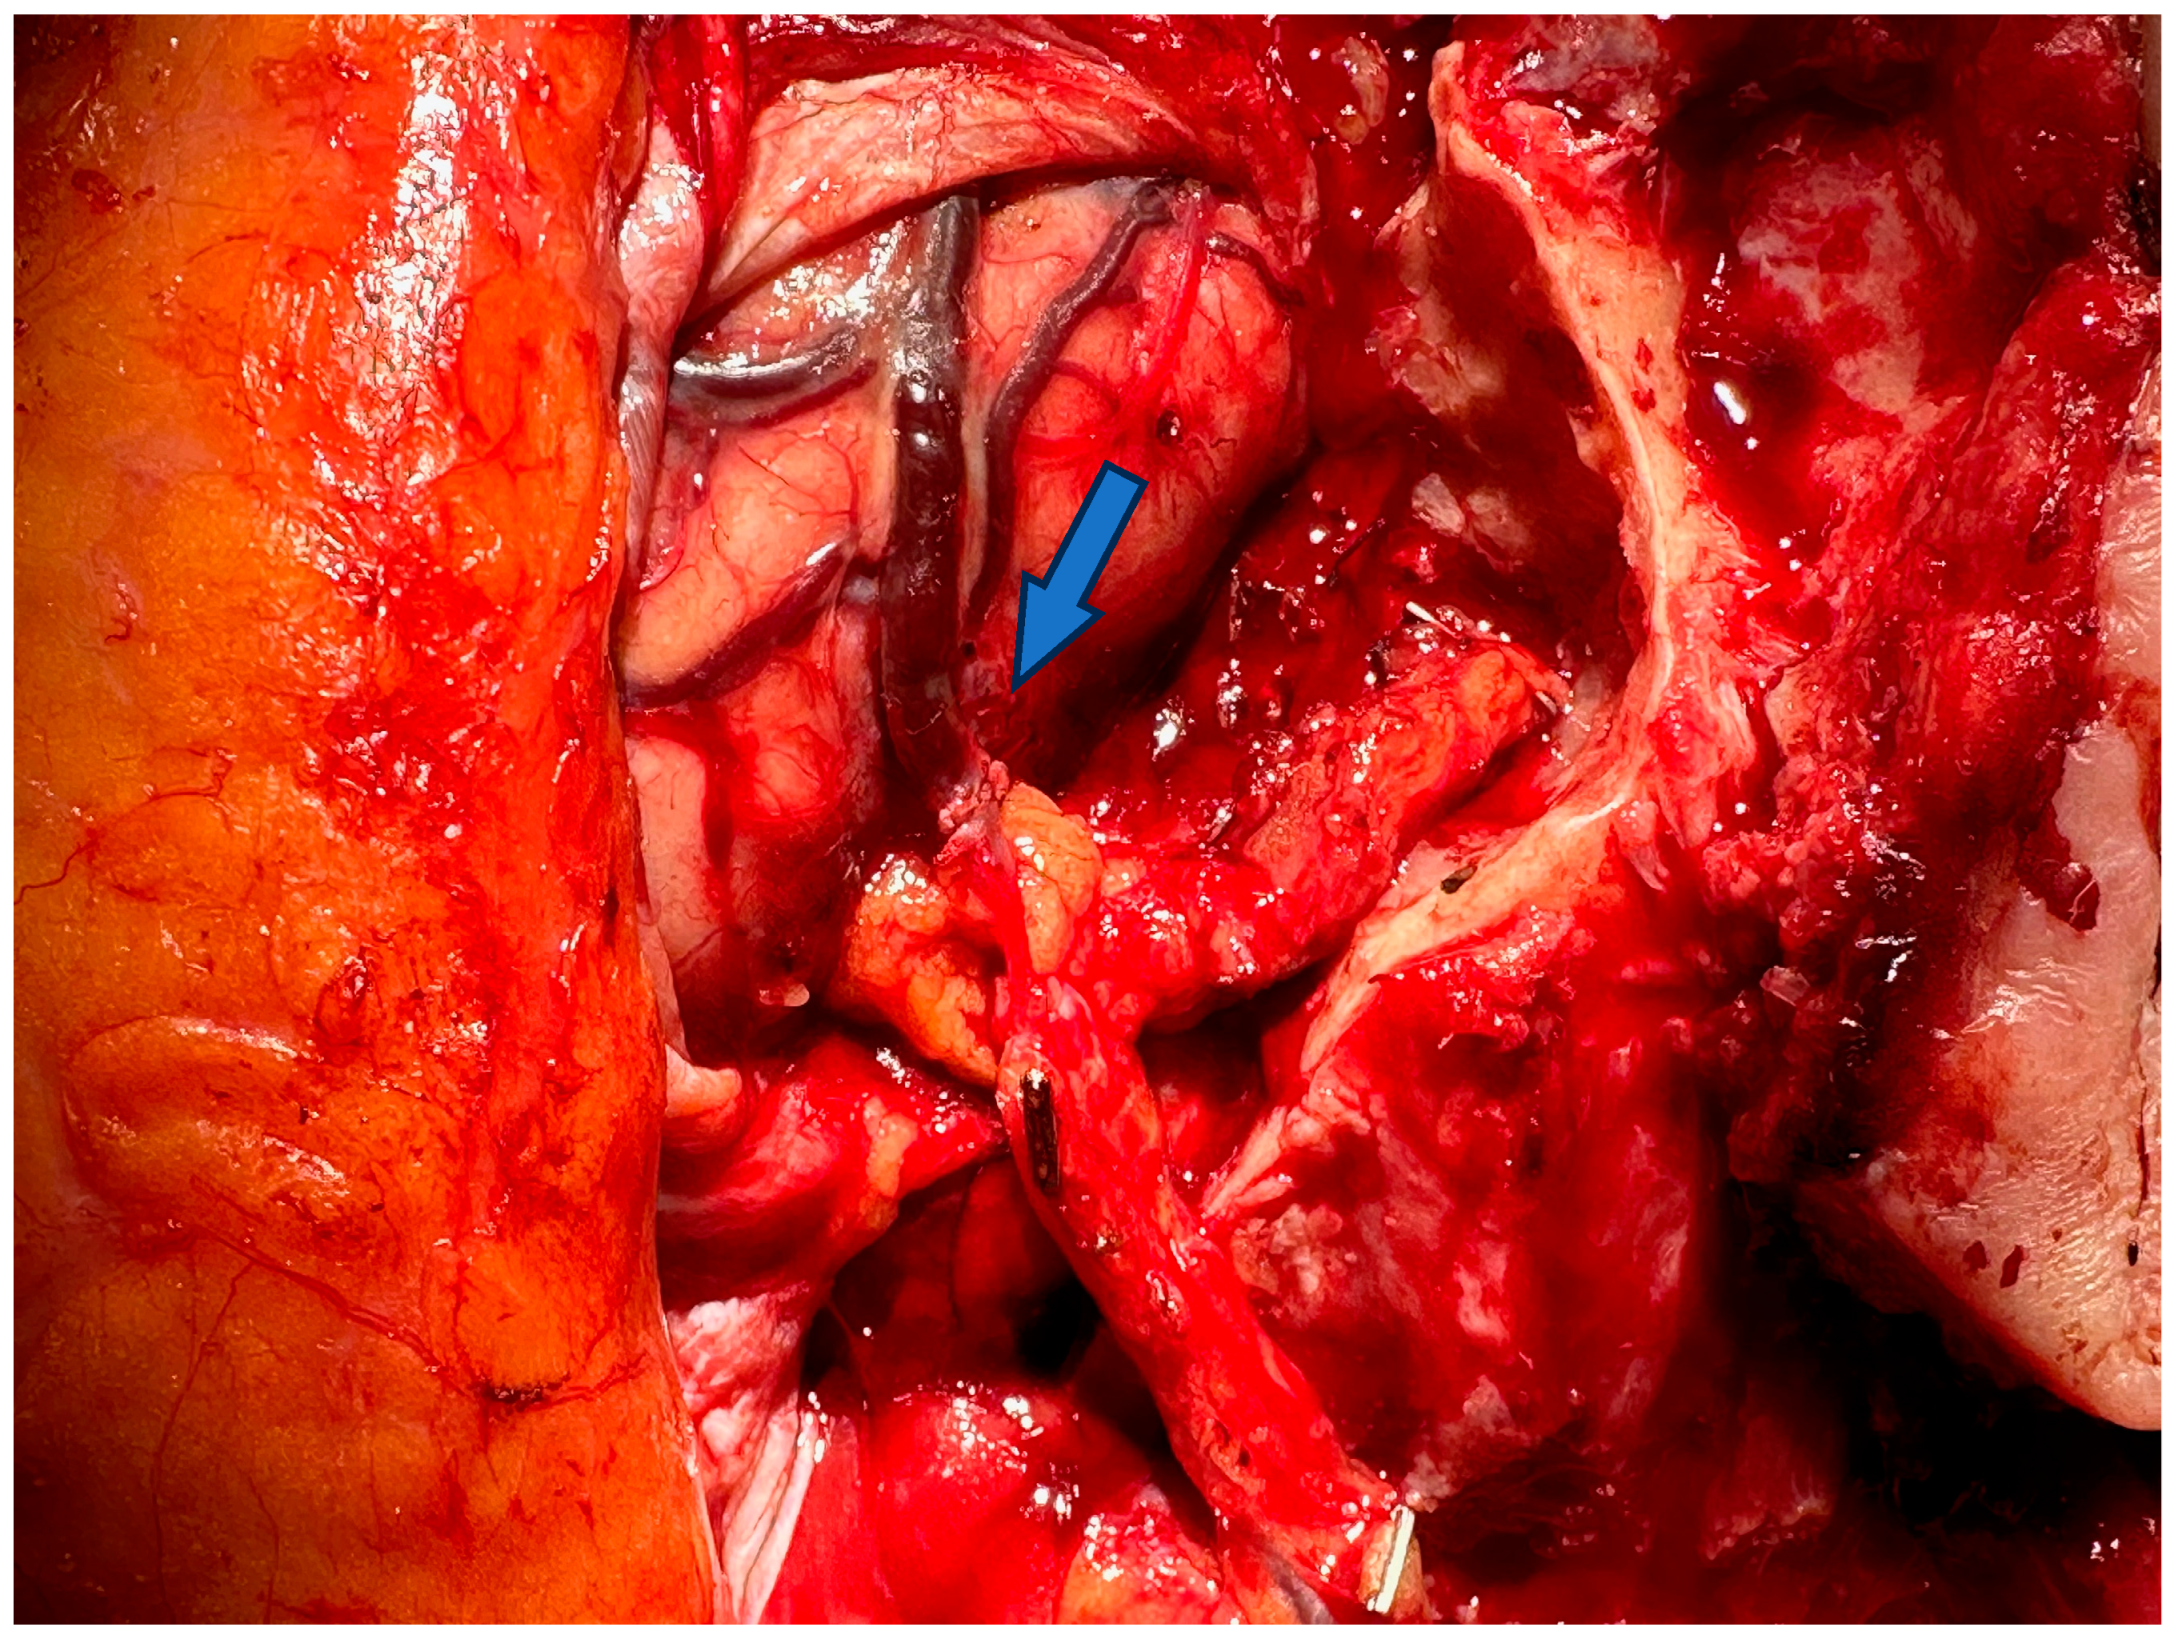

3.1. Advances in Diagnosis

3.2. Advances of Nerve Bridging and Transfer

4. Free Microsurgical Tissue Transfer